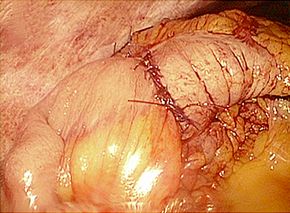

腹腔鏡手術で胆嚢の摘出と総胆管結石の摘除を同時に行います。胆嚢摘出後、十二指腸

上部総胆管を切開し、胆道鏡を用いて直視下に胆石を除去します。

採石後は胆道鏡で結石遺残のないことを確認します。その後胆管切開部を腹腔鏡下に

体内で結紮縫合を行い、閉鎖します。

術後創部写真(6ヶ月後)

腹腔鏡下総胆管切開結石除去術は高度な技術を要します。当院では検査を行い、適応を